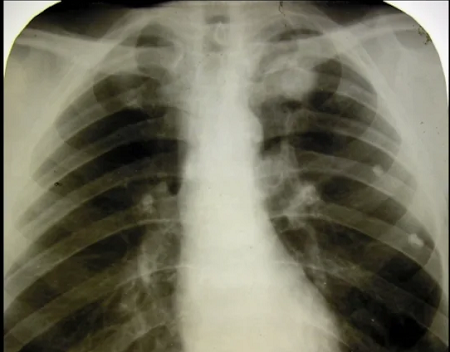

Семиотика. Рентген, КТ Термин применяют для описания видимой на рентгенограммах или на КТ/МРТ-срезах области уплотнения легочной ткани, вызванного поражением воздухосодержащей и/или интерстициальной ткани легкого (см.). Обычно такой участок имеет округлую или близкую к ней форму. Использование данного термина спорно, поскольку различные специалисты понимают его морфологический смысл по-разному. Например, рентгенолог может применить этот термин для описания воспалительного процесса, инфекционного или неинфекционного, либо злокачественного новообразования. Однако это совсем не означает, что речь действительно идет о воспалении (например, туберкулезный инфильтрат), а не об опухоли легкого. Нередко термин употребляется как синоним злокачественной опухоли с рентгенологическими признаками инфильтративного роста (нечеткие лучистые контуры, тяжи к плевре и ее утолщение, обрыв бронха в образовании и пр.). Таким образом, он не рекомендован к употреблению, поскольку для

Термин применяют для описания видимой на рентгенограммах или на КТ/МРТ-срезах области уплотнения легочной ткани, вызванного поражением воздухосодержащей и/или интерстициальной ткани легкого (см.). Обычно такой участок имеет округлую или близкую к ней форму. Использование данного термина спорно, поскольку различные специалисты понимают его морфологический смысл по-разному. Например, рентгенолог может применить этот термин для описания воспалительного процесса, инфекционного или неинфекционного, либо злокачественного новообразования.

Однако это совсем не означает, что речь действительно идет о воспалении (например, туберкулезный инфильтрат), а не об опухоли легкого.

Нередко термин употребляется как синоним злокачественной опухоли с рентгенологическими признаками инфильтративного роста (нечеткие лучистые контуры, тяжи к плевре и ее утолщение, обрыв бронха в образовании и пр.). Таким образом, он не рекомендован к употреблению, поскольку для описания большинства процессов опухолевого или воспалительного характера существуют другие термины. Предпочтительнее использовать термины «уплотнение», «образование», «очаг» (см.) с различными уточняющими характеристиками процесса.